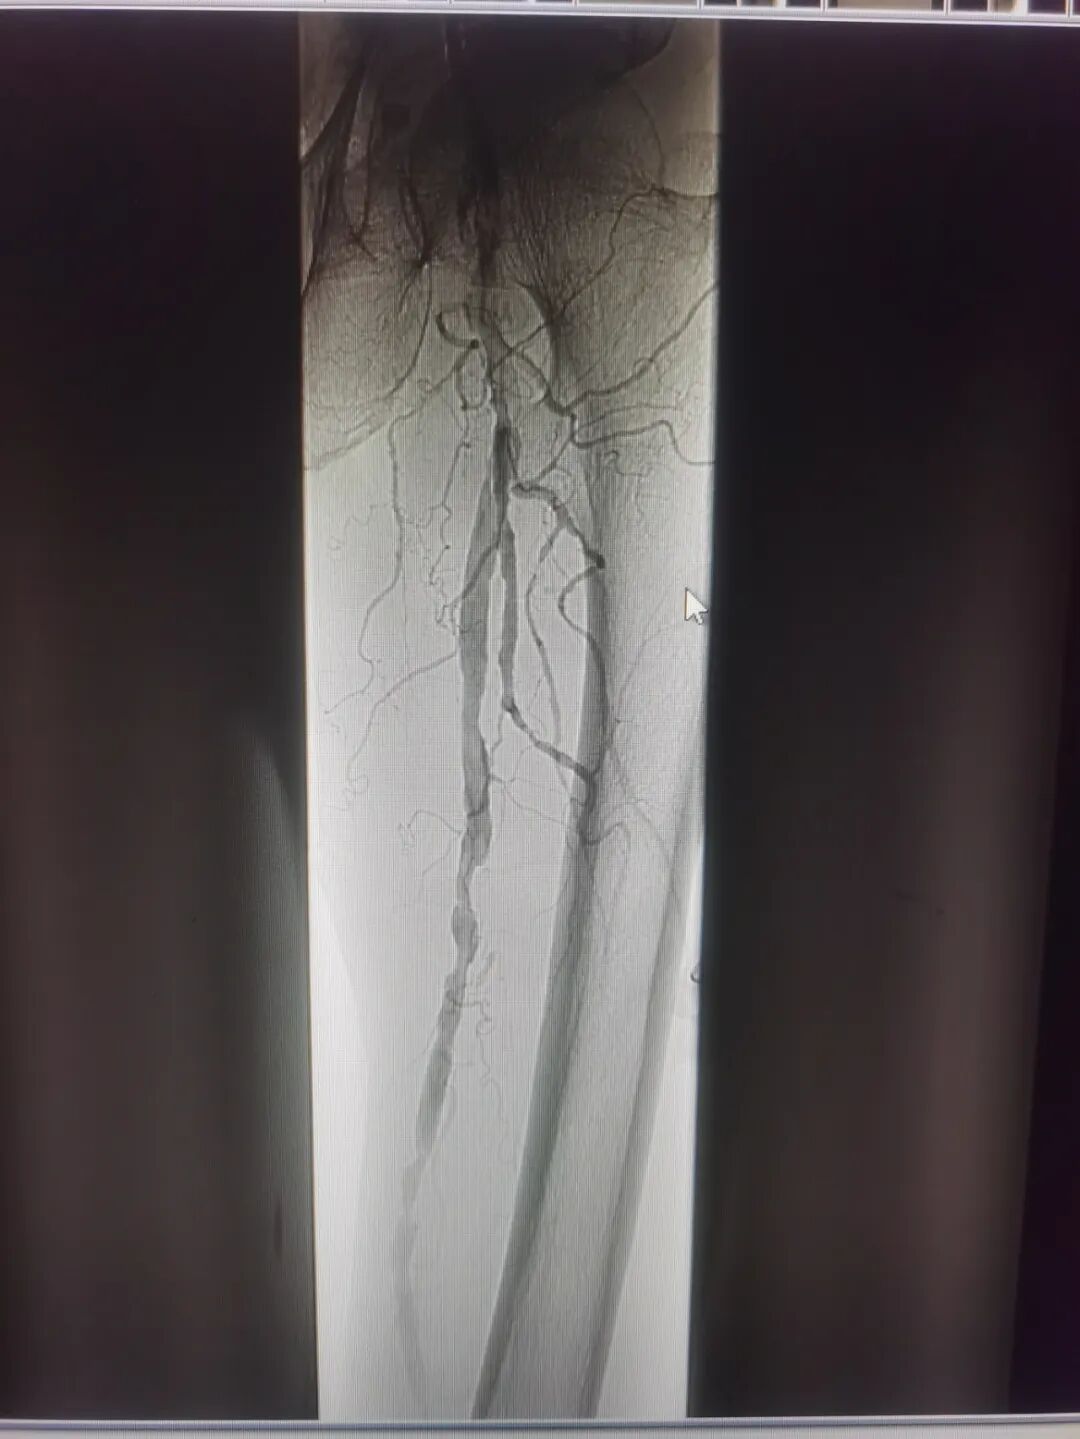

术中造影

考虑到患者病情严重,如果不及时手术恢复血管通畅,患者将面临截肢的风险,创伤外科主任刘立华、副主任医师陈国政向患者及其家属详细交代了病情,决定为患者实施手术治疗。在广东医科大学附属医院血管甲状腺乳腺外科主任医师张智的指导下,陈国政副主任医师联合介入科刘德副主任医师、曹传越医师等顺利为患者完成左髂动脉狭窄球囊扩张、左股浅动脉狭窄球囊扩张及支架成形术、左胫前动脉闭塞开通及球囊扩张成形术,手术完成后逐段造影显示患者左胫前动脉通畅,远端血流明显加快。经手术治疗后,患者左足肿胀较前消退,足背创面已较前好转,远端血运较前改善,顺利出院,治疗效果满意。